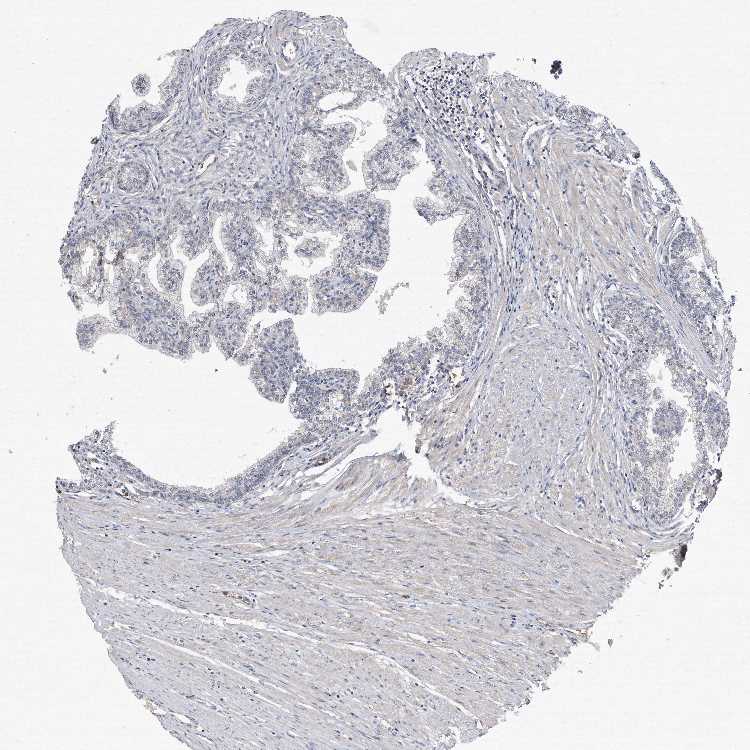

PROSTATE - Antibody stainingi

Antibody staining in the annotated cell types in the current human tissue is reported as not detected, low, medium, or high, based on conventional immunohistochemistry profiling in selected tissues. This score is based on the combination of the staining intensity and fraction of stained cells.

Each image is clickable and will lead to virtual microscopy that enables deeper exploration of all samples and also displays staining intensity scores, fraction scores and subcellular localization as well as patient and tissue information for each sample.

Antibody HPA040999Antibody CAB032656

Glandular cells Not detectedNot detected